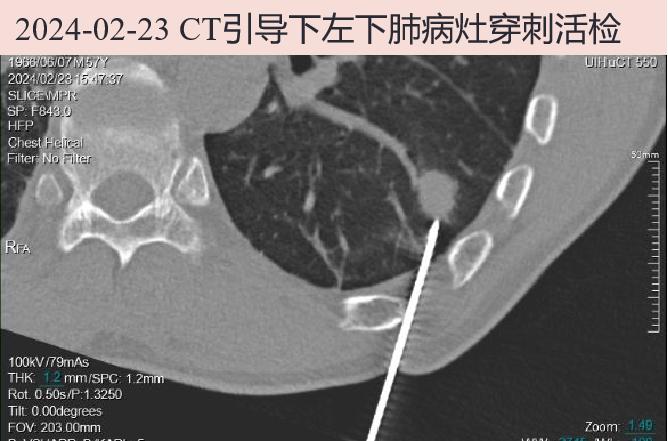

2024-02-23 左下肺结节病灶考虑肿瘤性病变不排除,故经CT引导下左下肺病灶穿刺活检。